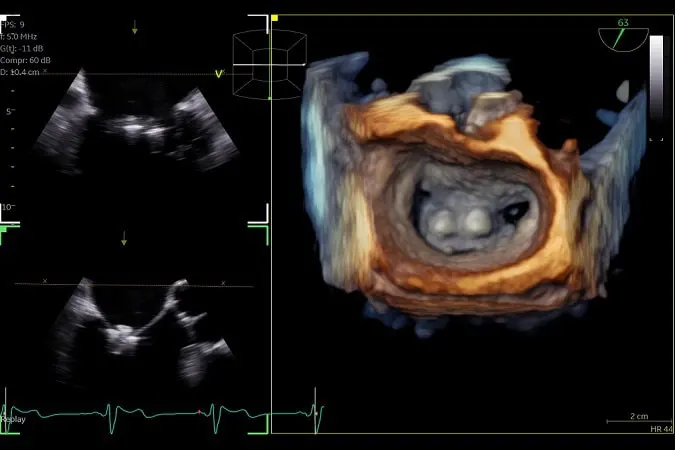

Η επέμβαση γίνεται διαδερμικά, δηλαδή χωρίς στερνοτομή και εξωσωματική κυκλοφορία, μέσω ειδικού καθετήρα που προωθείται στην καρδιά από τη μηριαία φλέβα. Συνήθως, η επέμβαση πραγματοποιείται υπό ολική αναισθησία και διαρκεί περί τις 2 ώρες. Καθ’ όλη τη διάρκεια της επέμβασης διενεργείται τρισδιάστατο διοισοφάγειο ηχωκαρδιογράφημα που καθοδηγεί βήμα προς βήμα τον επεμβατικό καρδιολόγο για την τοποθέτηση του clip. Το Clip (MitraClip/PASCAL) λειτουργεί μέσω συμπλησίασης και πρόσδεσης των γλωχίνων της μιτροειδούς βαλβίδας και οδηγεί σε σημαντική μείωση και συχνά πλήρη εξάλειψη της ανεπάρκειας. Ο ασθενής παραμένει στην εντατική για 1 ημέρα και παίρνει εξιτήριο στις επόμενες 48 ώρες. Τα ποσοστά επιτυχίας αυτής της μεθόδου είναι εξαιρετικά, με σχεδόν το 100% των ασθενών να μη χρειάζονται περαιτέρω μελλοντικές παρεμβάσεις στη μιτροειδή βαλβίδα.